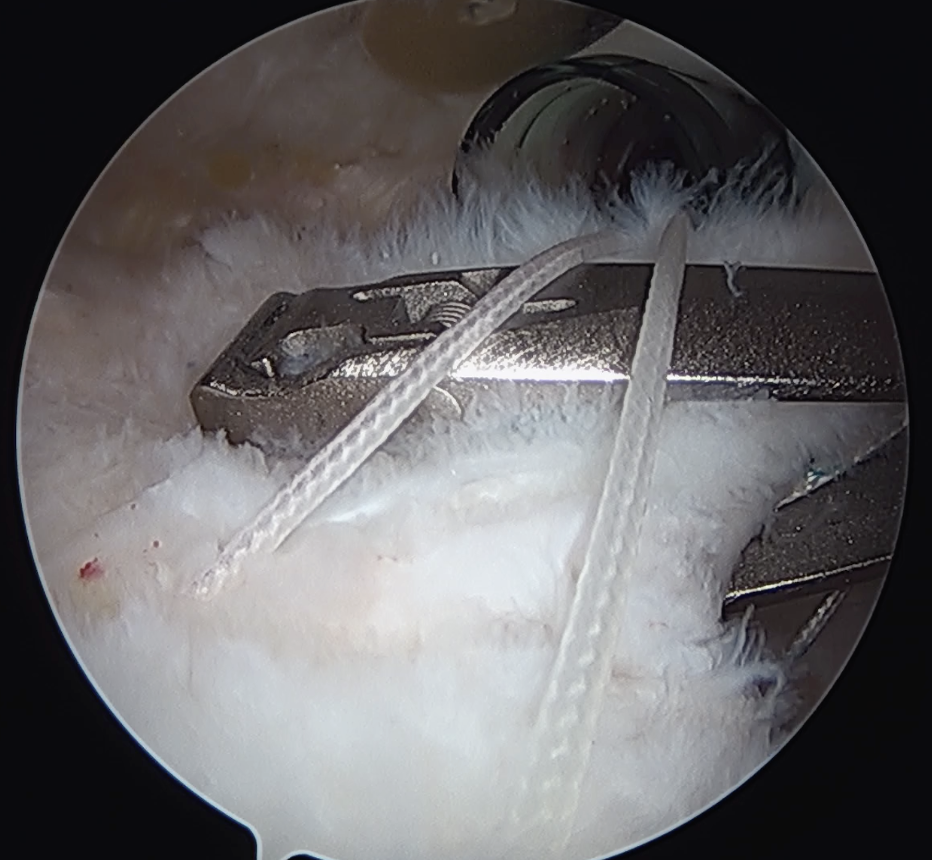

Trans-osseous equivalent / suture bridge

- cross sutures from medial row to lateral row

- increase contact between cuff and footprint

Double row / suture bridge

- use medial row sutures

- secure in knotless lateral row anchors